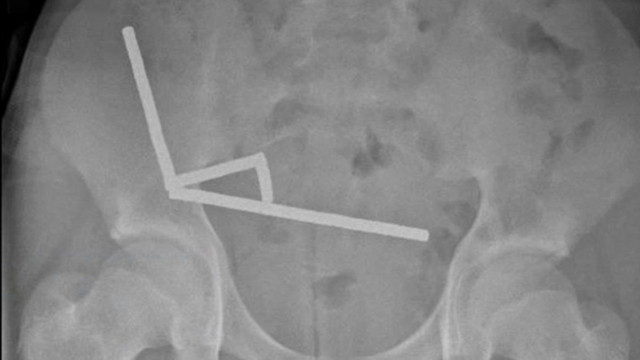

Ακτινογραφία έδειξε τέσσερις γραμμικές αλυσίδες μαγνητών σε διαφορετικά σημεία του εντέρου. Μέσα στην κοιλιά του, οι μικροί μεταλλικοί μαγνήτες ενώθηκαν με καταστροφικό τρόπο.